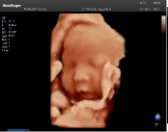

4容積探頭

積探頭是在二維圖像的基礎(chǔ)上,將連續(xù)采集的空間分布位置,經(jīng)過(guò)計(jì)算機(jī)重建算法,從而獲得完整的空間形態(tài)。

適用于:胎兒面部、脊柱和肢體等。

優(yōu)勢(shì)特點(diǎn):快速獲取、掃查連續(xù)均勻、解剖結(jié)構(gòu)顯示為容積數(shù)據(jù)、準(zhǔn)確進(jìn)行容積測(cè)量。